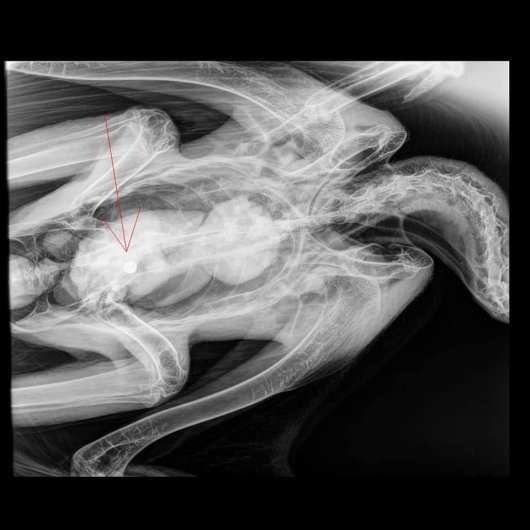

Η Ξανθίππη Παρασκευά μέλος της Οικολογική Ομάδας Ροδόπης μιλώντας αποκλειστικά στον «Χ» πληροφόρησε. «Η κτηνίατρος έκανε ακτινογραφίες. Στο σώμα του ζώου και υπήρχε βλήμα από αγριογούρουνο στο σώμα του. Αρχικά υποθέσαμε ότι πυροβολήθηκε ο γύπας. Τον στείλαμε λοιπόν για νεκροψία στην Θεσσαλονίκη και το βλήμα βρέθηκε στο έντερο του πουλιού. Αυτό σημαίνει ότι κατά πάσα πιθανότητα ο γύπας τράφηκε με κάποιο ψόφιο αγριογούρουνο και μαζί με την σάρκα κατάπιε και το βλήμα», δήλωσε μεταξύ άλλων.

Βέβαια ακόμα βρισκόμαστε σε αναμονή για την επίσημη γνωμάτευση μήπως ο θάνατος του πουλιού οφείλεται και σε άλλα αίτια. «Σίγουρα αυτό το βλήμα που βρέθηκε στο έντερο του, του δημιούργησε πρόβλημα» συμπλήρωσε η κα. Παρασκευά.